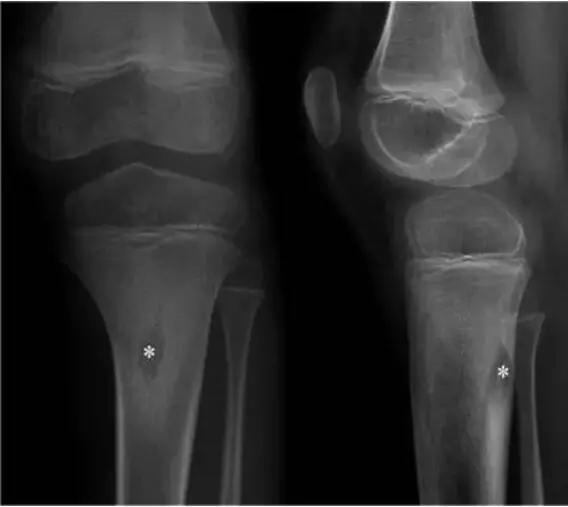

X线入门:几种骨肿瘤及肿瘤样病变的X线平片表现

568x507 - 14KB - JPEG